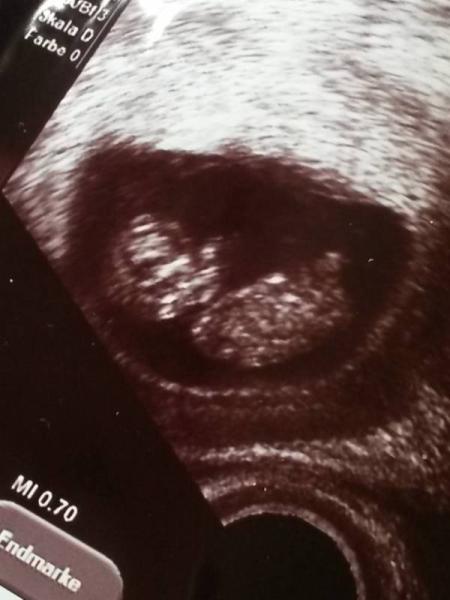

Wir kommen grade von der Ärztin und haben den Krümel heute zum ersten Mal per Ultraschall gesehen Es ist alles bestens, 3,5cm groß und war fleißig am turnen

Bild zu Zurück von der Ärztin :) - Forum für Februar - Mamis